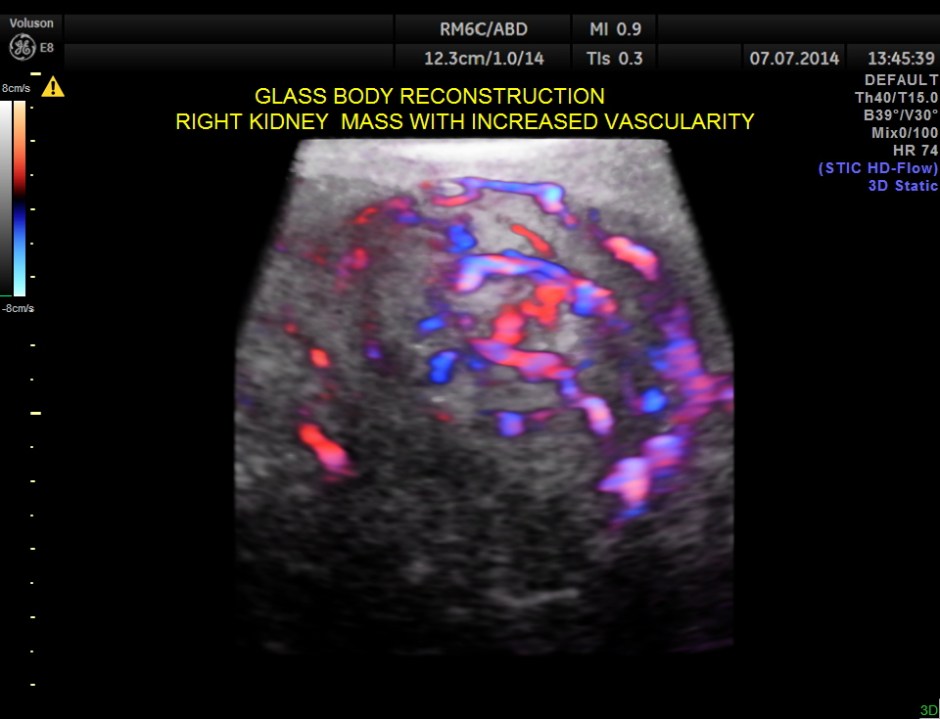

The right kidney is shown below. A solid mass is seen in the lower pole region.

The mass shows increased vascularity on Power Doppler.

GLASS BODY RECONSTRUCTION shows increased vascularity.

In this patient the increased vascularity is brought out very well by glass body imaging . Clots of blood seen in the urinary bladder gave the false impression of a mass lesion in the bladder initially.The importance of a dynamic study of turning the patient to the sides should always be remembered.